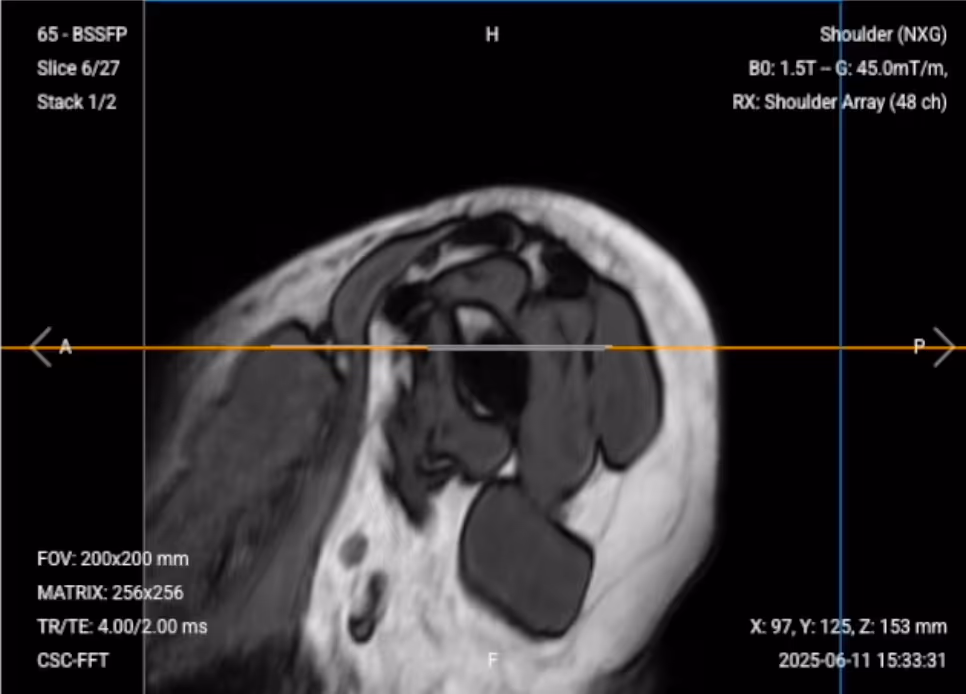

✅ Sagittal Localizer – Correct Image Example:

✅ Coronal Localizer – Correct Image Example:

✅ Axial PD Fat-Sat Localizer – Correct Image Example: